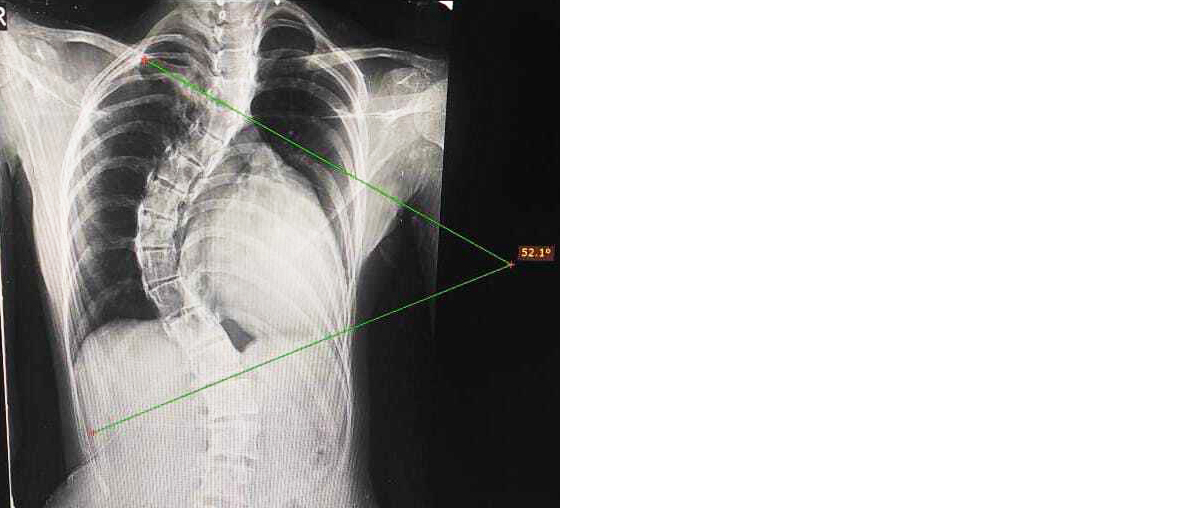

Computed tomography (CT) of the lumbosacral spine revealed levoscoliosis at the L3–L4 level with a Cobb’s angle of 52°, along with reduced intervertebral disc spaces, consistent with a diagnosis of idiopathic scoliosis (Figure 1). The child underwent surgical correction with corrective osteotomy and placement of cobalt–chrome rods and pedicle screws between L3–L4 and S1–S2 under image intensifier (IITV) guidance. Wound closure was performed with drain placement, and one unit of packed red blood cells (PRBC) was transfused intraoperatively. The postoperative period was uneventful, and the child recovered well.

Figure 1: Chest X-ray (PA view) showing scoliosis with measurement of Cobb’s angle.